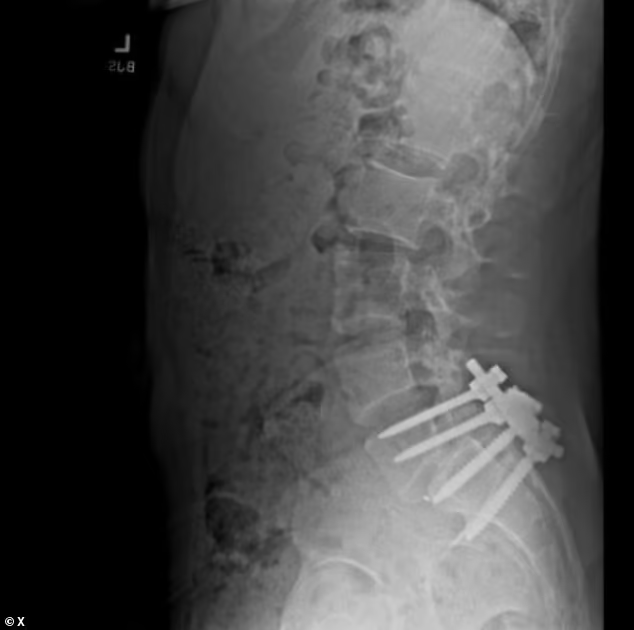

虽然家中有钱,但前两年在夏威夷冲浪伤到脊椎后,路易吉·曼吉奥饱受手术和病痛折磨,脊椎里插着好几根钢钉,这使他难以过上正常的生活,性格也开始大变。而且他母亲本身也有慢性疼痛,从小到大看着母亲和保险公司“打交道”,保险公司还找各种理由拖延到最后还拒保。